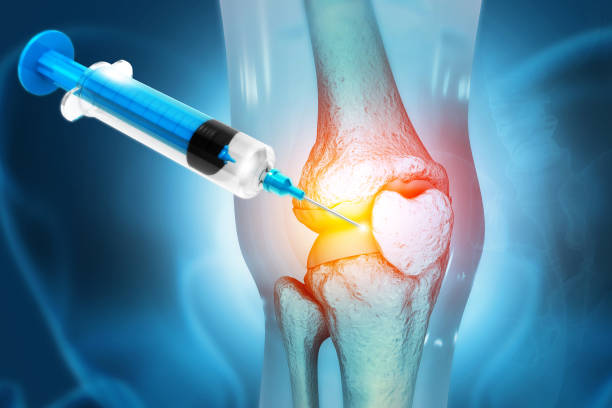

- 연골 주사: 연골 주사는 연골의 치료를 돕는데 사용될 수 있으며, 통증 완화와 연골 재생을 목표로 합니다.